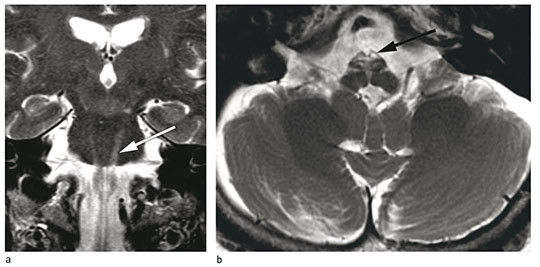

Det ble beskrevet symmetrisk signalavvik og atrofi ventralt i medulla oblongata, svarende til pyramidebanen. Signalavviket fortsatte sidelikt oppover i pons, men mesencephalon var spart. Forandringene strakte seg nedover i medulla spinalis til midttorakalt nivå. I tillegg var det symmetriske høysignalforandringer i nucleus dentatus cerebelli på T2-vektede bilder (fig 1).

Etter revurdering av kliniske funn, bildediagnostikk og tidligere utredning ble det konkludert med at tilstanden kunne minne om sent debuterende Alexanders sykdom.